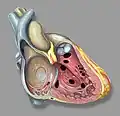

Heart anatomic view of right ventricle and right atrium with example ventricular septal defects -

Ventricular septal defect -

Figure A shows the structure and blood flow in the interior of a normal heart. Figure B shows two common locations for a ventricular septal defect. The defect allows oxygen-rich blood from the left ventricle to mix with oxygen-poor blood in the right ventricle.